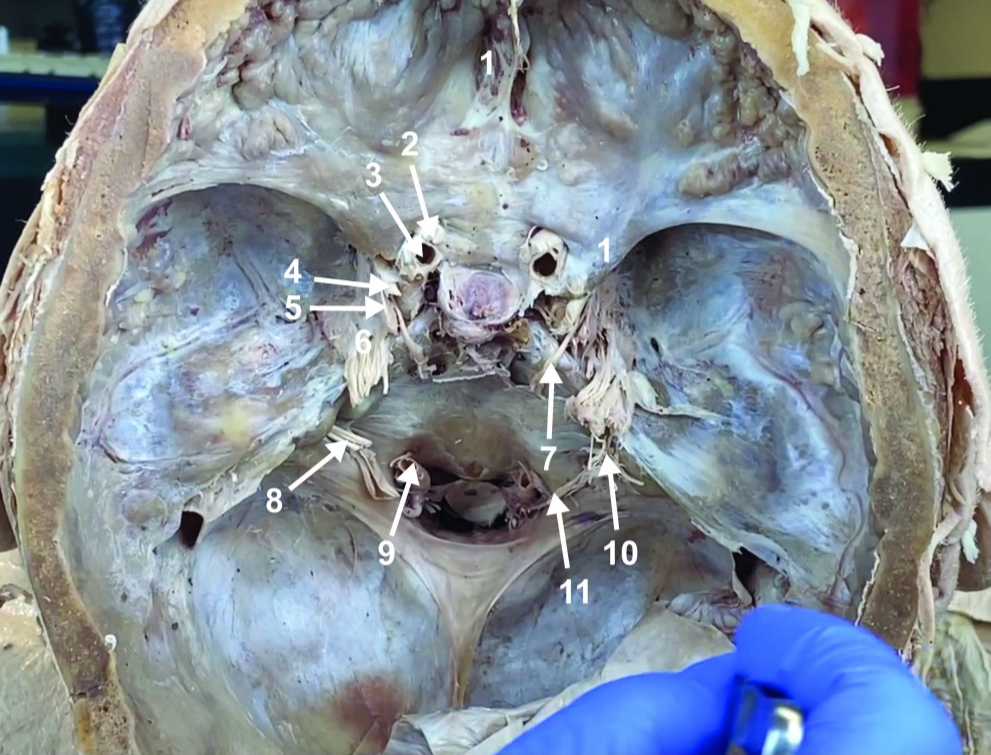

Foramen magnum

ID structure

Foramen ovale

ID structure

Foramen spinosum

ID structure

Cribiform plate

ID structure

Optic n. (CN II)

ID structure

Internal carotid a. (ICA)

ID structure

Occulomotor n. (CN III)

ID structure

Trochlear n. (CN IV)

ID structure

Trigeminal n. (CN V)

ID structure

Abducent n. (CN VI)

ID structure

Facial and vestibulocochlear n. (CN VII and VIII)

ID structure

Vertebral a.

ID structure

Glossopharyngeal and vagus n. (CN IX and X)

ID structure

Root of spinal accessory n. (root of CN XI)

ID structure

Ophthalmic division of CN V (CN V1)

ID structure

Maxillary division of CN V (CN V2)

ID structure

Mandibular division of CN V (CN V3)

ID structure

Foramen rotundum

ID structure

Foramen ovale

ID structure

Trochlear n. (CN IV)

ID structure

Abducent n. (CN VI)

ID structure